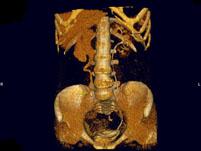

问题 女,44岁,突发性胁腹部绞痛并向会阴部放射伴血尿一次。如图所示,下列说法正确的是 ( )

选项 A、右输尿管结石 B、左肾输尿管未见异常 C、右输尿管中上段扩张 D、右输尿管内可见沿输尿管走行的高密度影 E、右侧肾盂肾盏扩张

答案 ABCDE